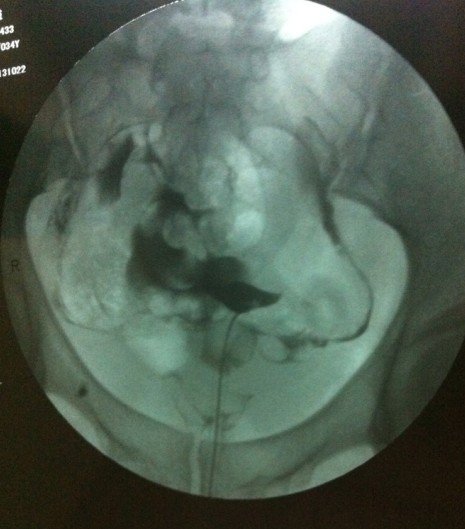

34岁,没流过产也没怀过孕,月经周期40天左右 造影的诊断结果为:两侧输卵管上举,伴通而不畅 请问 怎么样才能治好,中医可以治好吗? 点击展开 匿名用户 2013-11-10 09:40 为您推荐: 其他回答 病情分析: 你好,中医效果不大的。 指导意见: 可以考虑腹腔镜手术来治疗,术后注意不可过早恢复同房,及时复查。 独水凡_xjeq 2013-11-10 10:08 相关问题 想要二胎,两年未孕,月经不调去医院检查做输卵管造影是通而极不畅,吃了两个月的中药,又做了输卵管通液 卵泡成熟用了药和促排卵针还是没排,输卵管通,月经周期正常…怎么治,要吃药打针多久才有改善? 女性输卵管不通,月经周期正常,在此情况下用药店购买的排卵测试纸,能测试出女性是否正常排卵吗?